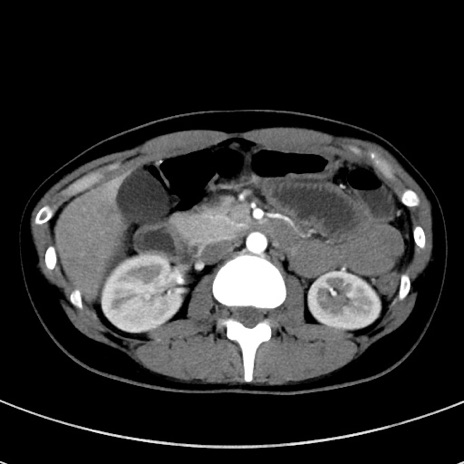

症例17(横断像)

【症例】20歳代女性

【主訴】嘔吐、下腹部痛

【現病歴】昨日夕食後に嘔吐し下腹部痛が出現。本日になっても嘔吐持続し改善しないため来院。

【身体所見】意識清明、BT 37.2℃、BP 108/67mmHg、腹部:平坦、やや硬、下腹部正中から右にかけて圧痛あり、反跳痛軽度あり、tapping pain(+)。

【データ】WBC 13600、CRP 14.94